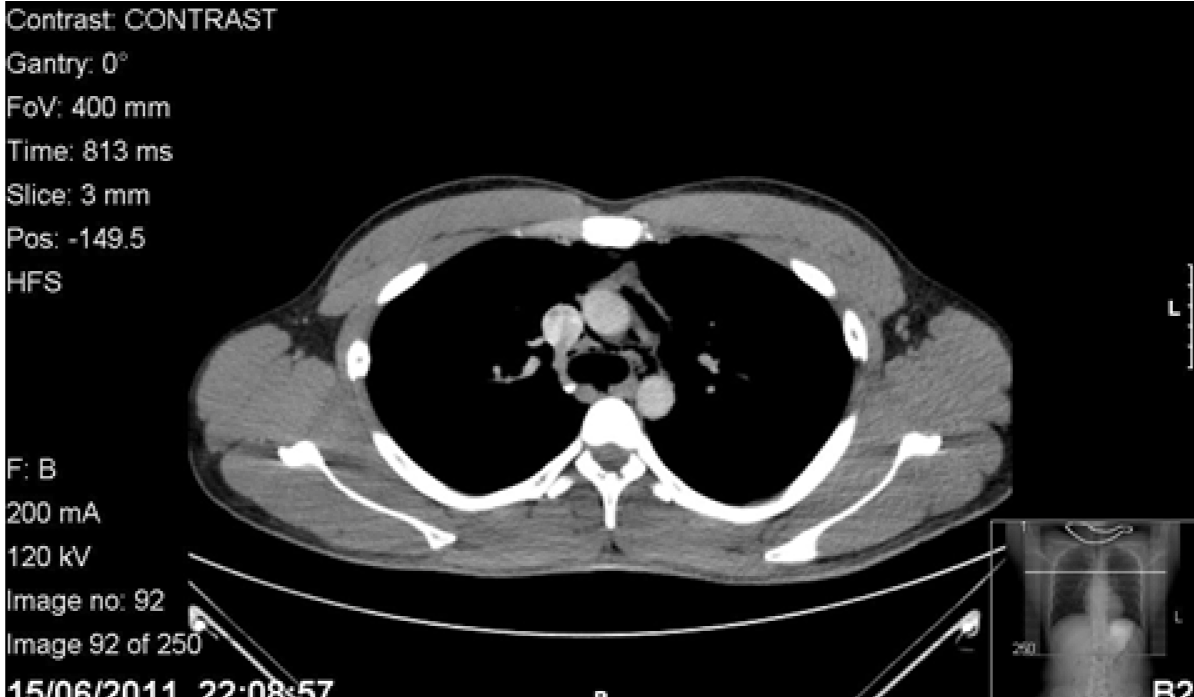

The patient returned home. However while taking his dinner, he experienced severe odynophagia describing the sensation like ‘swallowing glass’. The following day, his symptoms persisted so he consulted his surgical tutor whose registrar palpated the subcutaneous emphysema in his neck with no lymphadenopathy. An urgent X-ray of the neck revealed air in the subcutaneous tissues. Computed tomography (CT) scan of chest with contrast and Gastrografin swallow revealed a small leak outside the esophagus and pneumomediastinum. (Figure 1) Blood tests were unremarkable. The patient was transferred to a tertiary upper gastrointestinal centre with suspected Boerhaave’s syndrome. The tear was thought to be in the upper third of the esophagus. He was kept nil by mouth, supplemented with intravenous fluids and given prophylactic daily intravenous tazocin, metronidazole and fluconazole. Gastrografin swallow on the fifth day revealed no obvious leak, his symptoms had resolved. The patient was discharged with advice of a liquid diet for one week building to solids slowly thereafter.

Figure 1: Computed tomography scan of chest with Gastrografin contrast on initial admission illustrating a pneumomediastinum with leak of contrast into mediastinum.